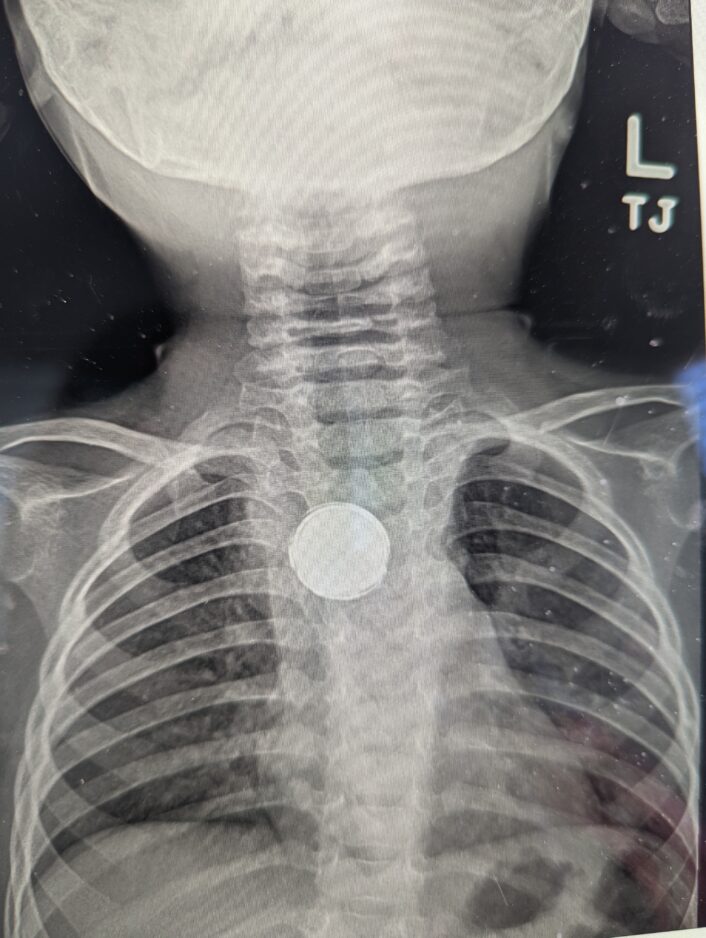

- This X-ray photo shows a battery in the esophagus of 1-year-old Luke McMillan.

The issue persisted, so Luke’s parents took him back to the doctor, only to be told he had acid reflux, but that didn’t sit right with them, so they continued to persist for answers. This time, an X-ray was taken and within five minutes, Luke was sent to the emergency room where the battery was removed.